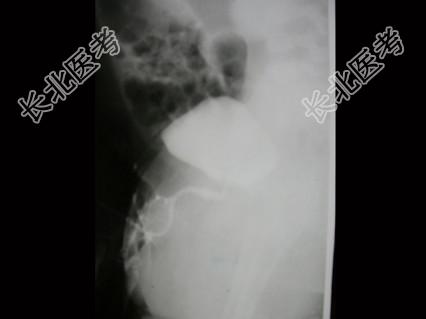

- 单项选择题男,4个月, 阴茎、排尿异常4个月,行尿道造影如图所示, 最可能的诊断是 ( )

A、正常尿道

B、尿道瓣膜形成

C、尿道下裂畸形

D、尿道憩室

E、尿道重复畸形